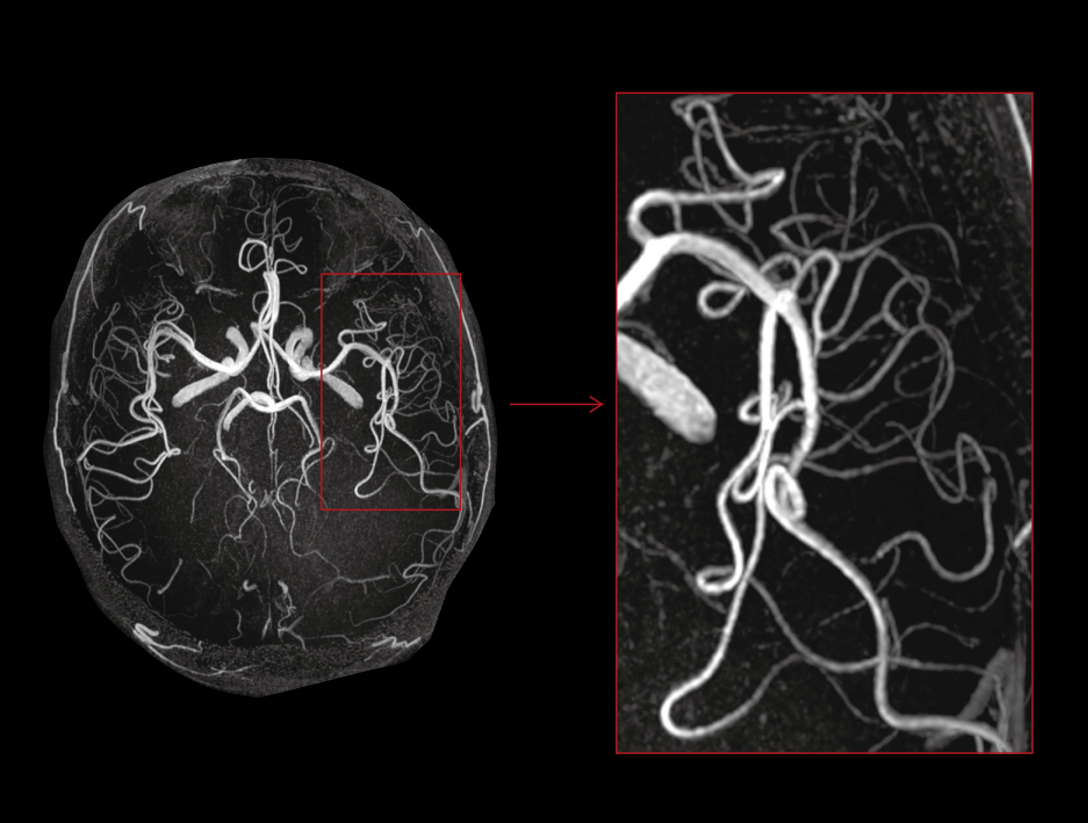

The high performance gradients improve data acquisition and scanning speed, which achieves higher work efficiency.

The 48 high-channel RF complements our integrated high-density coils, resulting insignificant image SNR increase.

The powerful 3.0T magnet uses a 170 cm short-magnet design to ensure high homogeneity of the magnetic field, which provides a solid foundation for fast imaging and excellent fat saturation over a large FOV, as well as outstanding off-center imaging.